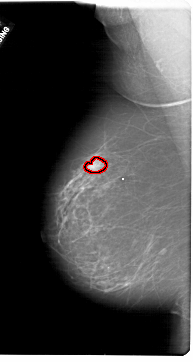

FILE: A_1778_1.LEFT_MLO.OVERLAY

TOTAL_ABNORMALITIES 1

ABNORMALITY 1

LESION_TYPE MASS SHAPE LOBULATED MARGINS CIRCUMSCRIBED

ASSESSMENT 4

SUBTLETY 5

PATHOLOGY BENIGN

TOTAL_OUTLINES 1

BOUNDARY